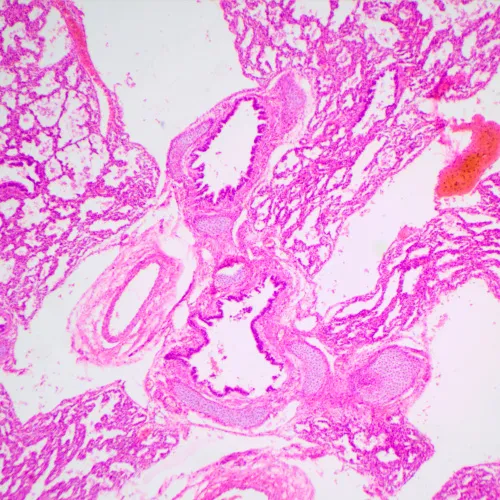

The microscope is suitable for observing transparent and translucent biological samples, such as smears and cross sections using the brightfield microscopy technique in transmitted light. The coded revolving nosepiece maintains a comfortable brightness level when the objectives are changed. The microscope's intelligent lighting control system improves comfort and speed of the researcher’s everyday work. Smart features help students ease into the profession and gain the professional experience they need. Practical aspects play an important role for student microscopes. The size, weight, ease of storage of the cords, and the microscopes themselves are important in everyday use. This microscope is convenient to move around on a table due to its small dimensions and low weight. It does not take up much space in storage. It is equipped with a 2MP camera with an HDMI interface. The digital camera outputs the image directly on the monitor screen with no connection to a computer. The software complements the system with analysis and documentation functions. The monitor in the digital microscope has Full HD resolution.

- Observations of transparent and translucent samples in brightfield in transmitted light